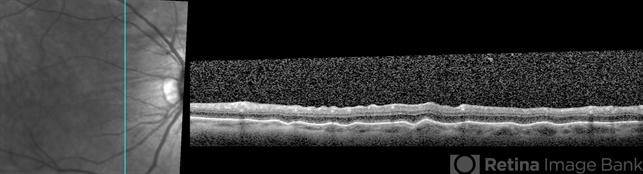

- choroidal folds

- Optical coherence tomography system

- 61-year-old male with choroidal folds